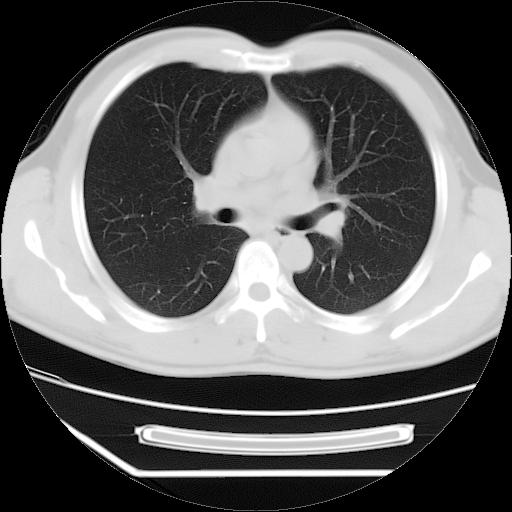

男,38岁,于2009年8月9日晚突发左侧胸痛,今x线提示左下肺阴影,为了明显确诊断,行ct检查,

血常规:嗜酸性细胞增高,单核细胞增高。

病灶发生在下叶,密度均匀,边缘模糊、毛糙,周围血管纹理增强扭曲改变,靠近胸膜处病灶胸膜反应明显。

支持考虑---球形肺炎。

左肺舌叶病变。主体病灶呈类圆形中心密度低,成液化趋势周边班片影分布

考虑肺脓肿

虽然实验室检查支持炎性病变,且病变内有坏死改变(中央呈大片状低密度影),但仍不能掉以轻心,鳞癌也可以有这种影像改变。